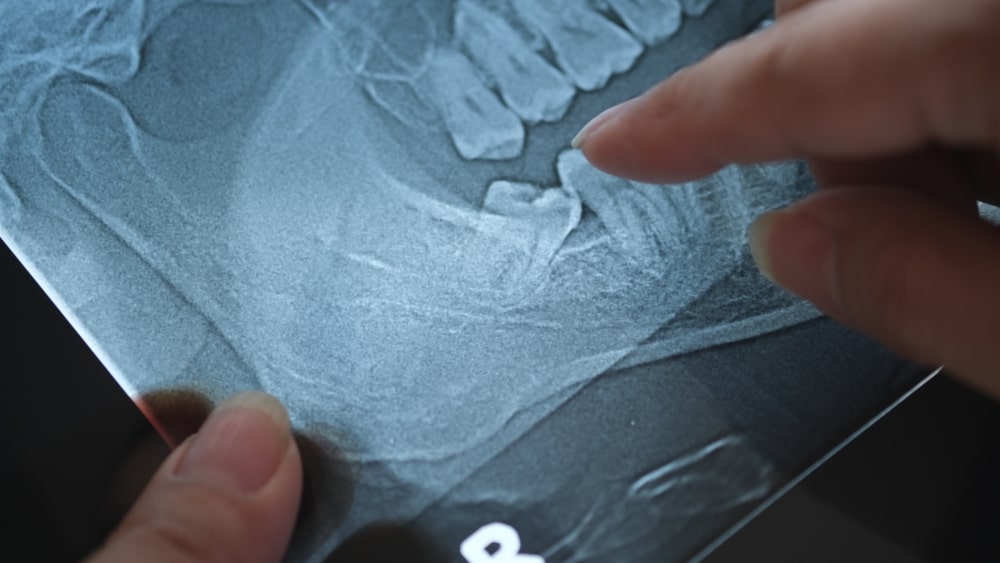

Wisdom teeth are the last set of molars to emerge, typically surfacing between the ages of 17 and 25. Because the jaw is often already full, these teeth may have limited space to grow, leading to misalignment or impaction. That can result in discomfort, infection, or damage to surrounding teeth.

• Risk of impaction: May stay fully or partially trapped beneath the gums

Wisdom tooth removal is often recommended to prevent more serious oral health problems. Impacted or overcrowded wisdom teeth can affect alignment, increase the risk of infection, and make daily hygiene more difficult. Extraction is a preventive step that keeps your mouth healthy and functional.